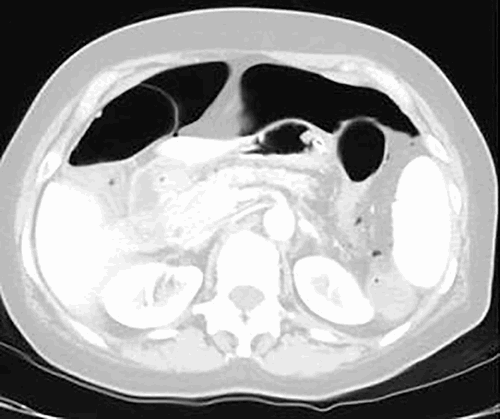

On postpartum day five, the patient returned to the ED with signs of sepsis and multiple organ failure. She was complaining of severe abdominal pain that had been progressively worsening for five days, nausea and vomiting, subjective fever, chills, sore throat, dyspnea, chest pain, palpitations, weakness, diffuse muscle cramps and lower leg edema. Her last BM was on the day of readmission, it was liquid and unclear if it was bloody because of postpartum vaginal bleeding. Her labs were unremarkable except for a leukocytosis of nineteen and renal failure with a BUN of 54 and creatinine of 2.7. On examination, the patient appeared very fatigued and drowsy, tachycardia was noted with a regular rhythm. The abdomen was grossly distended, diffusely tender with rebound and guarding. There were hypoactive bowel sounds and tympany present. The rest of the physical exam was unremarkable. Abdominal CT scan showed pneumoperitoneum.

Figure 2. CT scan of abdomen done in ED on admission, lung window.